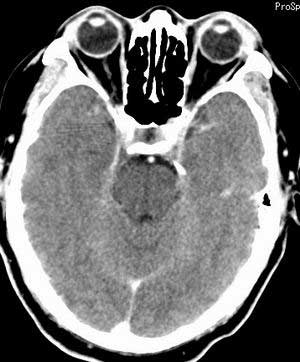

患者男,58岁。耳爆震伤后耳聋2年余,而后双耳道肿胀,间断性流脓。近一月来头痛、恶心、呕吐,右眼红痛,不能入眠。

在平扫时,见右侧枕骨下方小脑半球表面带状模糊稍高密度影,考虑为耳源性脑内感染。

平扫右侧岩骨与枕骨交角内侧脑质内见淡片状密度增高影,内缘清晰。增强图象上未见明显显示。

右枕颅骨内板下高密度应该是窦的变异,和其症状应该无关,根据病史另找原因吧。[em16]

建议行mr检查排除右枕硬膜下脓肿可能。

条状高密度为小脑幕吧

条状高密度为小脑幕

横窦乙状窦。

增强的横窦乙状窦。